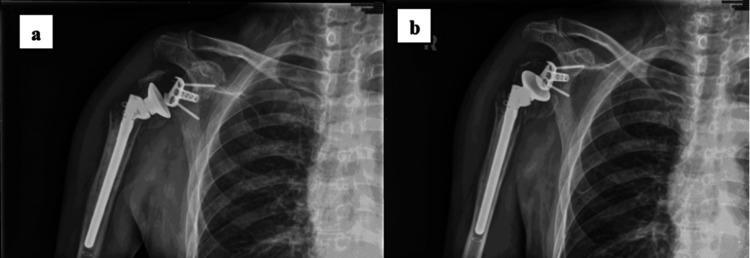

The aging population is witnessing a steady increase in the incidence of displaced proximal humerus fractures, particularly among elderly patients. Such fractures pose a significant challenge to orthopedic surgeons, given the complex interplay of factors involved, including fracture displacement, comminution, compromised bone quality, and the presence of concurrent medical comorbidities. While open reduction internal fixation (ORIF) remains a viable treatment option for these fractures, it is a technically demanding procedure associated with a high incidence of complications. Recently, reverse total shoulder arthroplasty (RTSA) with tuberosity repair has gained popularity as a successful approach for addressing such fractures. The present case report details a unique and complex case of a chronic four-part proximal humerus fracture, complicated by avascular necrosis of the humeral head, fracture non-union, and hardware penetration. The patient was successfully treated through a reverse shoulder arthroplasty procedure, highlighting the effectiveness of this surgical approach in such challenging scenarios. The advantages of RTSA in this context include the potential to address avascular necrosis, non-union, and hardware complications, as seen in our patient. Additionally, the procedure can restore functional independence and improve the overall quality of life in these challenging cases.

老年人口中肱骨近端移位骨折的发生率正在稳步上升,尤其是在老年患者中。鉴于涉及多种因素的复杂相互作用,包括骨折移位、粉碎、骨质受损以及并发内科疾病,此类骨折给骨科医生带来了重大挑战。虽然切开复位内固定术(ORIF)仍是治疗这些骨折的可行选择,但它是一项技术要求高且并发症发生率高的手术。最近,带结节修复的反式全肩关节置换术(RTSA)作为治疗此类骨折的成功方法而受到欢迎。本病例报告详细介绍了一例独特且复杂的慢性肱骨近端四部分骨折病例,该病例并发肱骨头缺血性坏死、骨折不愈合和内固定物穿透。该患者通过反式肩关节置换术成功治愈,突出了这种手术方法在这类具有挑战性的情况下的有效性。在这种情况下,RTSA的优势包括有解决缺血性坏死、不愈合和内固定物并发症的潜力,正如我们的患者所示。此外,该手术可以恢复功能独立性,并改善这些具有挑战性病例的整体生活质量。